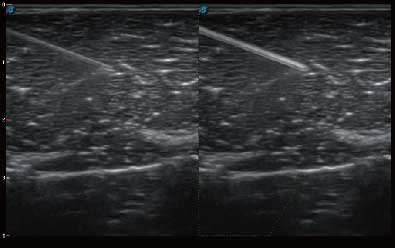

结合诸侯快讯官网超宽频带探头技术优势,能够更好地获得高分辨力与高穿透力的平衡,保证图像质量,为临床诊断保驾护航。

微米成像技术提升了对组织斑点噪声信号的抑制能力,并进一步强化边界信息,从而获得清晰图像。